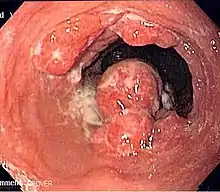

| Endoscopic image of an esophageal adenocarcinoma | |

Esophageal cancer is cancer arising from the esophagus—the food pipe that runs between the throat and the stomach.[2] Symptoms often include difficulty in swallowing and weight loss.[1] Other symptoms may include pain when swallowing, a hoarse voice, enlarged lymph nodes ("glands") around the collarbone, a dry cough, and possibly coughing up or vomiting blood.[1]

The two main sub-types of the disease are esophageal squamous-cell carcinoma (often abbreviated to ESCC),[9] which is more common in the developing world, and esophageal adenocarcinoma (EAC), which is more common in the developed world.[2] A number of less common types also occur.[2] Squamous-cell carcinoma arises from the epithelial cells that line the esophagus.[10] Adenocarcinoma arises from glandular cells present in the lower third of the esophagus, often where they have already transformed to intestinal cell type (a condition known as Barrett's esophagus).[2][11] Causes of the squamous-cell type include tobacco, alcohol, very hot drinks, poor diet, and chewing betel nut.[3][4] The most common causes of the adenocarcinoma type are smoking tobacco, obesity, and acid reflux.[3]